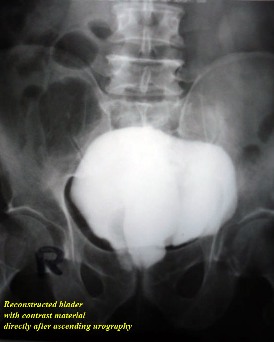

treatment. By difficulty we persuaded him to do ascending urography

" see photos".

Do you think that these photos were

convincing for the patient?